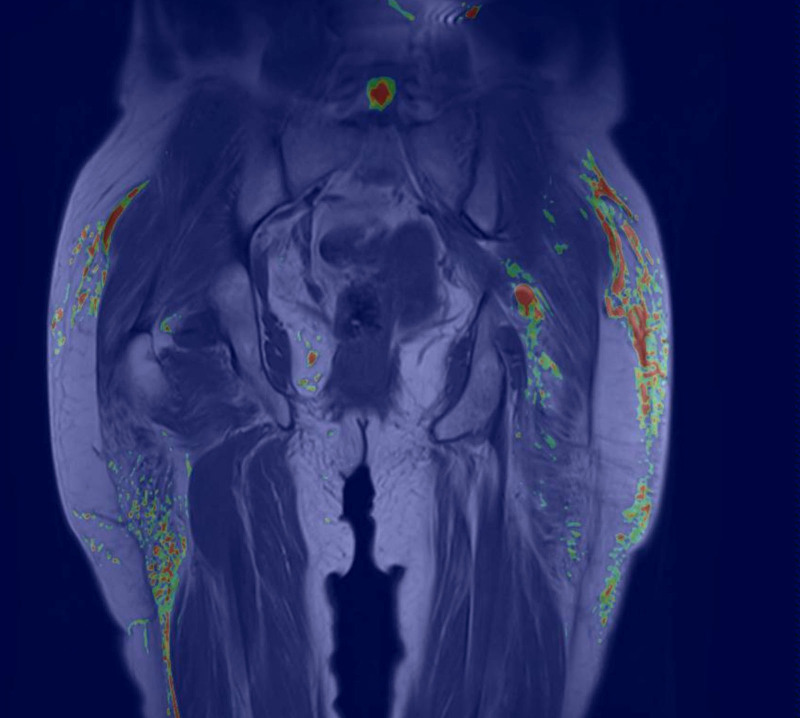

患者有臀区深度注射非药物物质(生物聚合物)的病史,导致坐骨神经受压。本文描述了从皮下组织、肌肉组织和坐骨神经中去除生物聚合物的外科技术。对目前的坐骨神经手术入路进行了结构化的回顾。详细介绍了临床病例的术前评价、术中技术及术后随访情况。所描述的手术入路有效地减压坐骨神经,从皮下组织和肌肉组织中去除生物聚合物材料,并改善症状、美容效果、恢复时间和额外手术的需要。鉴于生物聚合物去除和神经压迫的管理信息有限,该技术代表了一种可行的替代方案,在恢复和美容效果方面都有好处。

The patient presented with a history of deep injection of a nonmedical substance (biopolymer) into the gluteal region, resulting in compression of the sciatic nerve. The surgical technique used to remove biopolymers from the subcutaneous tissue, muscle tissue, and sciatic nerve is described. A structured review of the current surgical approaches for the sciatic nerve was conducted. The preoperative evaluation, intraoperative technique, and postoperative follow-up of the clinical case are detailed. The described surgical approach effectively decompresses the sciatic nerve, removes the biopolymer material from the subcutaneous tissue and muscle tissue, and improves symptoms, cosmetic outcomes, recovery time, and the need for additional surgery. Given the limited information on the management of biopolymer removal and nerve compression, this technique represents a viable alternative, offering benefits in recovery and cosmetic outcomes.